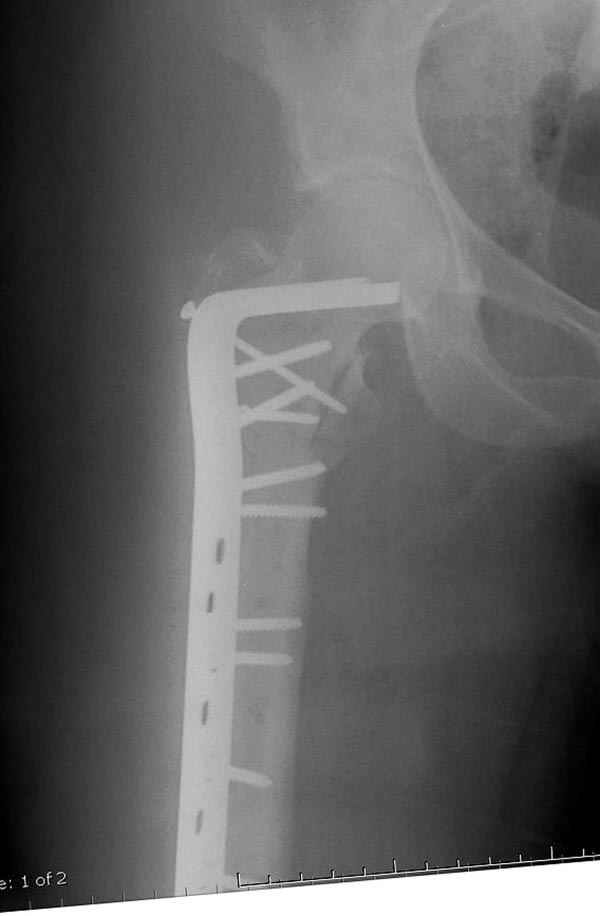

Как раз недавно у меня был примерный случай: больному 36 лет, поступил ночью, травма в результате мотоциклетной аварии, кроме чрезвертельного и спирального перелома левого бедра имеется переломы костей предплечья с этой же стороны. Скелетное вытяжение, а на следующий день больной про оперирован на ортопедическом столе с дистракцией. Чтобы не расколоть чрезвертельный перелом провели временную спицу ближе к переднему кортексу, из малого разреза костодержатель для репозиции, а фиксацию провели антиградным штифтом. Этапы операции на снимках.

Джолдас Кульджанов

Да, сейчас это и у нас самый напрашивающийся выбор. Сделали гвоздем ChM, картинки в приложении.